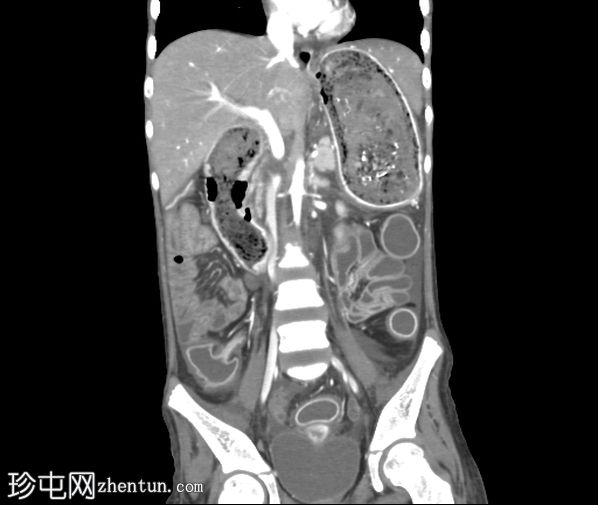

轴位增强扫描(门静脉期)

胃腔内可见巨大肿块,内含斑驳状软组织、气体和高密度灶,延伸至幽门、十二指肠和近端空肠(长发公主综合征)。十二指肠轻度扩张。

胃壁强化减弱及胃壁积气区域。

当胃石穿过幽门延伸至十二指肠和空肠时,这种情况被称为长发公主综合征。患者会出现腹痛、呕吐、早饱,有时还会出现体重减轻。CT 扫描具有很高的敏感性,可以显示管腔内肿块,其内部呈斑驳状气体分布,且在管腔造影剂的照射下边界清晰。